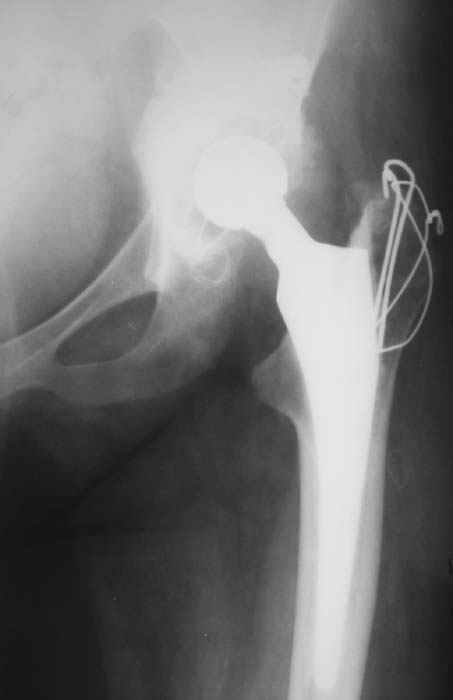

Уважаемые коллеги! Женщина, 28 лет. Страдает ревматоидным полиартритом, гормонозависима. 6 месяцев назад перенесла тотальное эндопротезирование левого тазобедренного сустава по поводу протрузионного коксита.

Использована цементная версия с пластикой дна впадины измельченной аутокостью и гранулами гидроксиапатита. Субъективное улучшение после операции. Улучшилось и стабилизировалось общее состояние. В настоящее время затруднено передвижение из-за поражения правого коленного сустава. Болезненный и <болтающийся> сустав. Предполагается замена сустава протезом без сохранения задней крестообразной связки. Возможные варианты? Заранее благодарю! С уважением,А.В.ВладзимирскийДонецкий НИИ травматологии и ортопедииДонецк, Украина